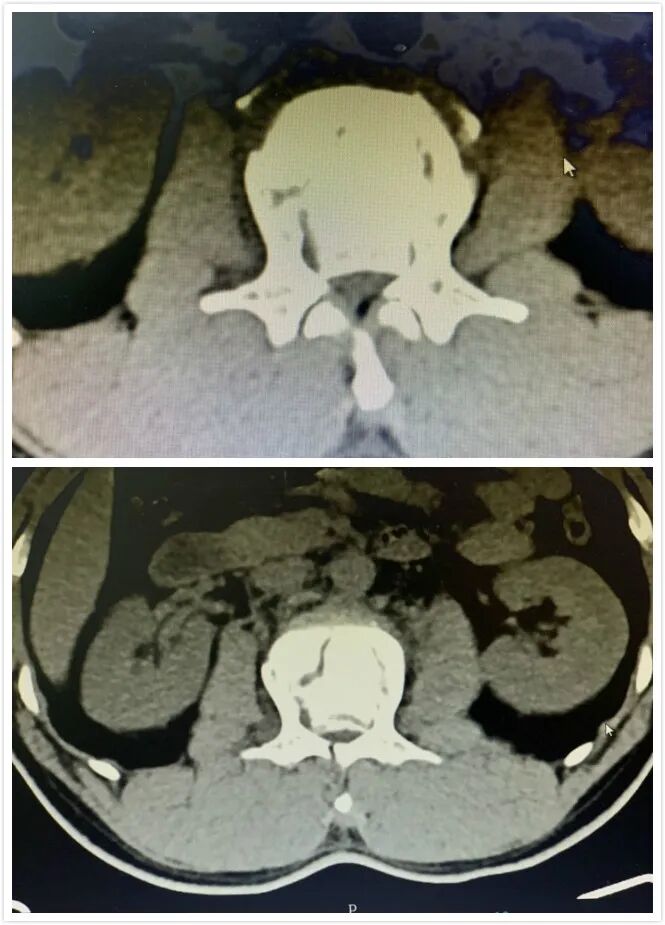

之后,我院骨外科安排对李先生做了进一步详细的检查,对患者病情做了更全面的评估。确诊李先生为2椎体爆裂性骨折,且碎裂的骨折块向后脱位占据了80%椎管面积,马尾神经受压,腰2棘突骨裂。

另外,双侧椎旁压痛,下腹壁、右侧提睾反射都消失了,右髂前上棘以下感觉麻木,右膝以下感觉消失。右下肢肌力2级,左侧提睾反射较弱,左腹骨沟以下感觉麻木,小腿以下麻木的感觉更加强烈,左下肢肌力3级,膝腱反射消失。

如果错过最佳治疗时机,则可能造成截瘫。我院骨外科专家团队,由副主任医师彭明、院长刘文松牵头,以及骨外科其他同仁一起,针对李先生的情况进行了会诊,决定立即对患者进行腰2椎板减压脊柱内固定手术。